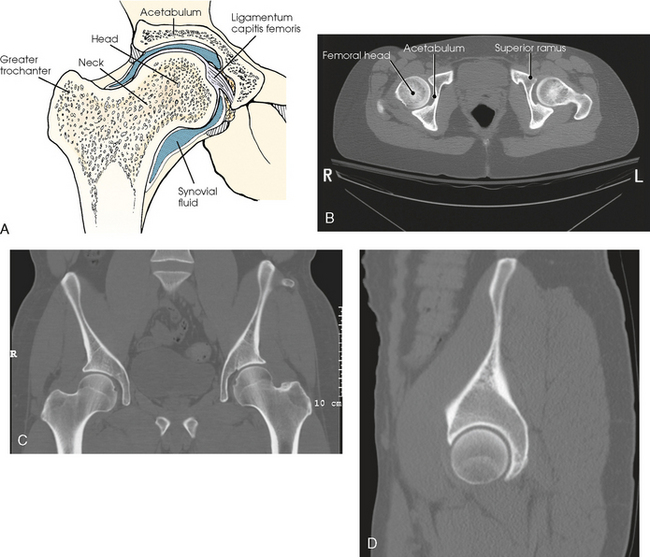

The hip bone consists of the ilium, pubis, and ischium (Figs. 7-1 and 7-2). These three bones join together to form the acetabulum, the cup-shaped socket that receives the head of the femur. The ilium, pubis, and ischium are separated by cartilage in children but become fused into one bone in adults.

The pubis consists of a body, the superior ramus, and the inferior ramus. The body of the pubis forms approximately one fifth of the acetabulum anteriorly (see Fig. 7-2). The superior ramus projects inferiorly and medially from the acetabulum to the midline of the body. There the bone curves inferiorly and then posteriorly and laterally to join the ischium. The lower prong is termed the inferior ramus.

The ischium consists of a body and the ischial ramus. The body of the ischium forms approximately two fifths of the acetabulum posteriorly (see Figs. 7-2 and 7-3). It projects posteriorly and inferiorly from the acetabulum to form an expanded portion called the ischial tuberosity. When the body is in a seated-upright position, its weight rests on the two ischial tuberosities. The ischial ramus projects anteriorly and medially from the tuberosity to its junction with the inferior ramus of the pubis. By this posterior union the rami of the pubis and ischium enclose the obturator foramen. At the superoposterior border of the body is a prominent projection called the ischial spine. An indentation, the lesser sciatic notch, is just below the ischial spine.